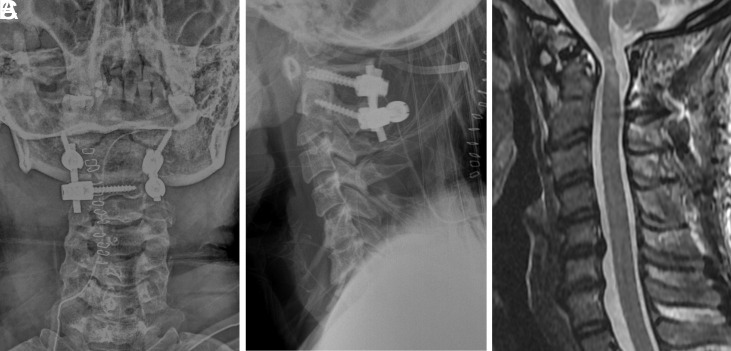

Vertebral arterial injury (VAI) remains a fatal complication of C1-C2 posterior screw fixation. Herein, we report asymptomatic bilateral VAI that was caused by screws following C1-C2 posterior fixation. A 34-year-old woman with cerebral palsy experienced quadriplegia after a fall. Cervical computed tomography (CT) showed increased ADI, with os odontoideum, for which C1 pedicle screw and C2 pedicle-lamina screw fixation were performed. Cervical magnetic resonance imaging (MRI) conducted for postoperative weakness in shoulder elevation demonstrated a well-decompressed spinal cord. However, neck CT angiography revealed bilateral vertebral artery (VA) violations by the C1 pedicle screw that induced occlusion of the V2 and V3 segments of both VA, with intact V4 segments. Diffusionweighted imaging showed no evidence of infarction. Cerebral angiography showed reconstitution of posterior circulation via the left fetal posterior communicating artery. Steroid treatment-induced improvement in shoulder elevation to the preoperative level, and no neurological deterioration has been detected for 3 years postoperatively. Prevention of VAI is one of the most important objectives when performing posterior cervical screw fixation. The screw should be inserted considering the rotation of C1 and C2. Notably, variations in cerebral circulation, which enable collateral blood flow to the posterior circulation, can lead to different sequelae in patients with iatrogenic VAI.